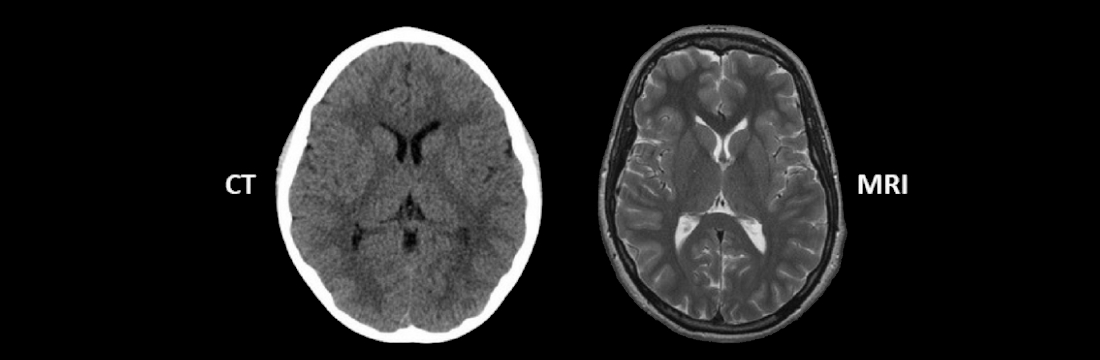

In the modern era, advanced diagnostic technology has significantly increased the diagnosis and treatment of various health conditions. Both CT and MRI scan is used to assess or diagnose a wide range of conditions.

Today CT scan and MRI scans is a common diagnostic tool which is used by doctors in day-to-day practice. For many of the people, the procedure looks the same but in reality they are very much different from each other in many aspects like methodologies, strengths and areas of application.

Computed tomography also known as CT scan or CAT scan. In a CT scan, an X-ray is used to create detailed images of the brain. CT scans are highly sensitive and swiftly capture detailed images of the skull, which shows fractures, bleeding and other bone-related problems. CT is much faster than MRI, and this rapid imaging is particularly useful in emergency situations where early assessment is crucial like in traumatic injuries of the brain or suspected bleeding in the brain.

On the other hand MRI (Magnetic Resonance Imaging ) Scan uses a powerful magnetic field and radio waves to create highly detailed images of soft tissues or organs. MRI is a preferred modality to evaluate the brain’s anatomy, nerves, blood vessels and brain tissues. MRI brain is a valuable diagnostic technique in detecting abnormalities such as tumours, strokes, multiple sclerosis, Alzheimer's disease and many more.